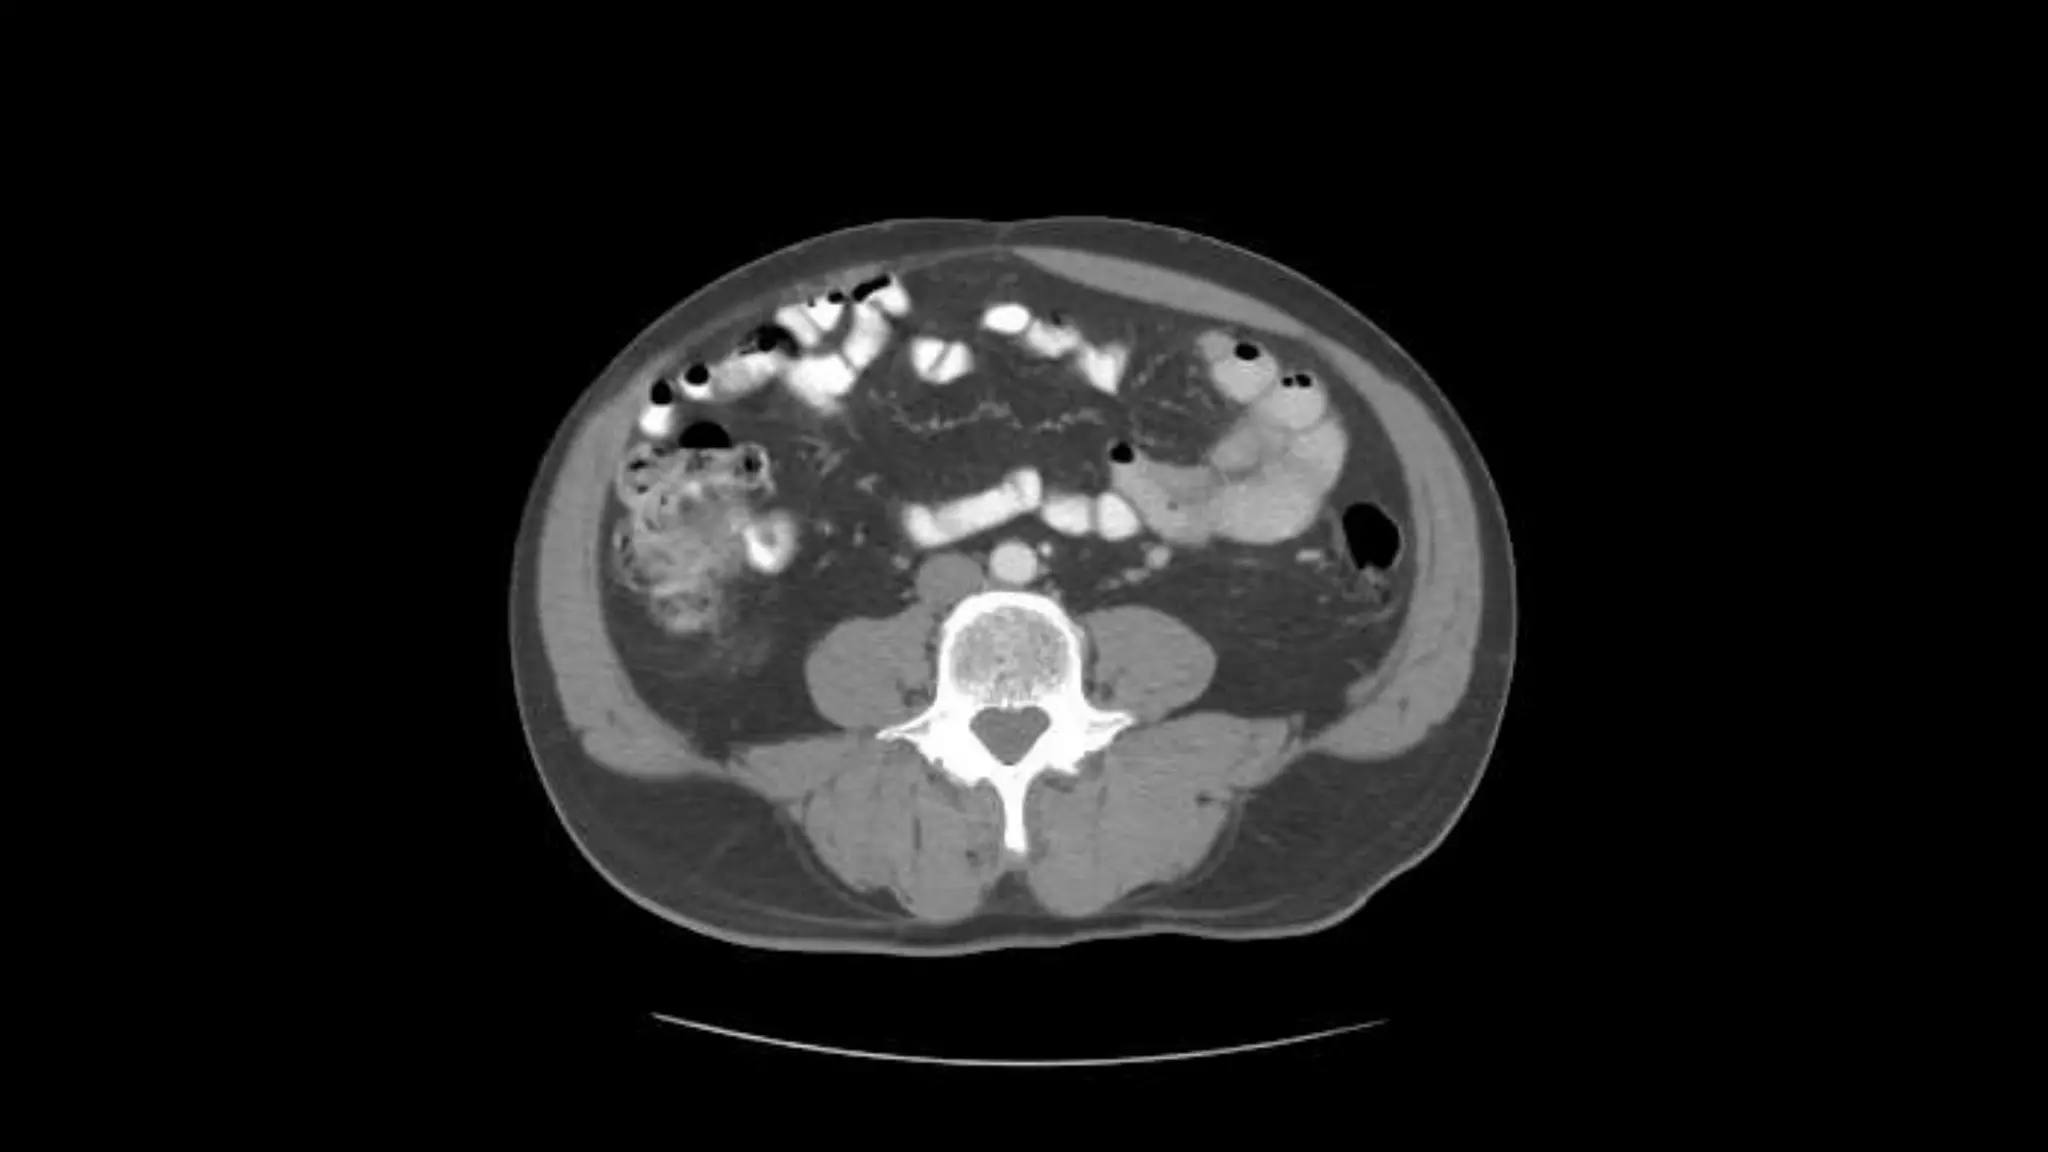

 In this sequence of images, we will label the abdominal vasculature.

The CT images are 5mm slices with soft tissue window settings. IV

and oral contrast have been administered which causes the vessels

and GI tract to appear hyperdense (white). Some images will contain

labels to assist with tracking the vessels.

Studying the CTimage  In this sequence of images, we will label the abdominal vasculature. The CT images are 5mm slices with soft tissue window settings. IV and oral contrast have been administered which causes the vessels and GI tract to appear hyperdense (white). Some images will contain labels to assist with tracking the vessels.  IMAGES ARE VIEWED AS LOOKING FROM THE FEET RIGHT LEFT